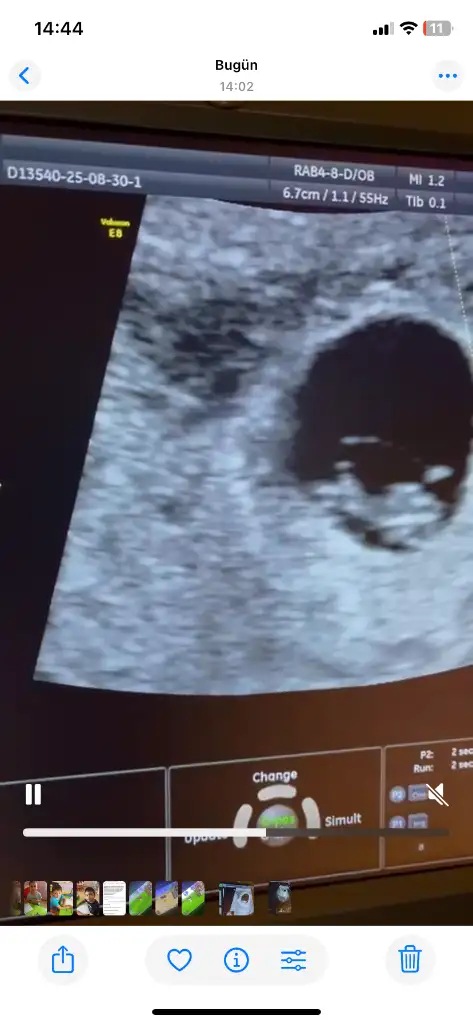

Bana da tahmin yaparmısınız

Eklentiler

• A6412A19-7D6F-4DC3-9149-FBE6D0210A9A.webp

A6412A19-7D6F-4DC3-9149-FBE6D0210A9A.webp

56,7 KB · Görüntüleme: 6